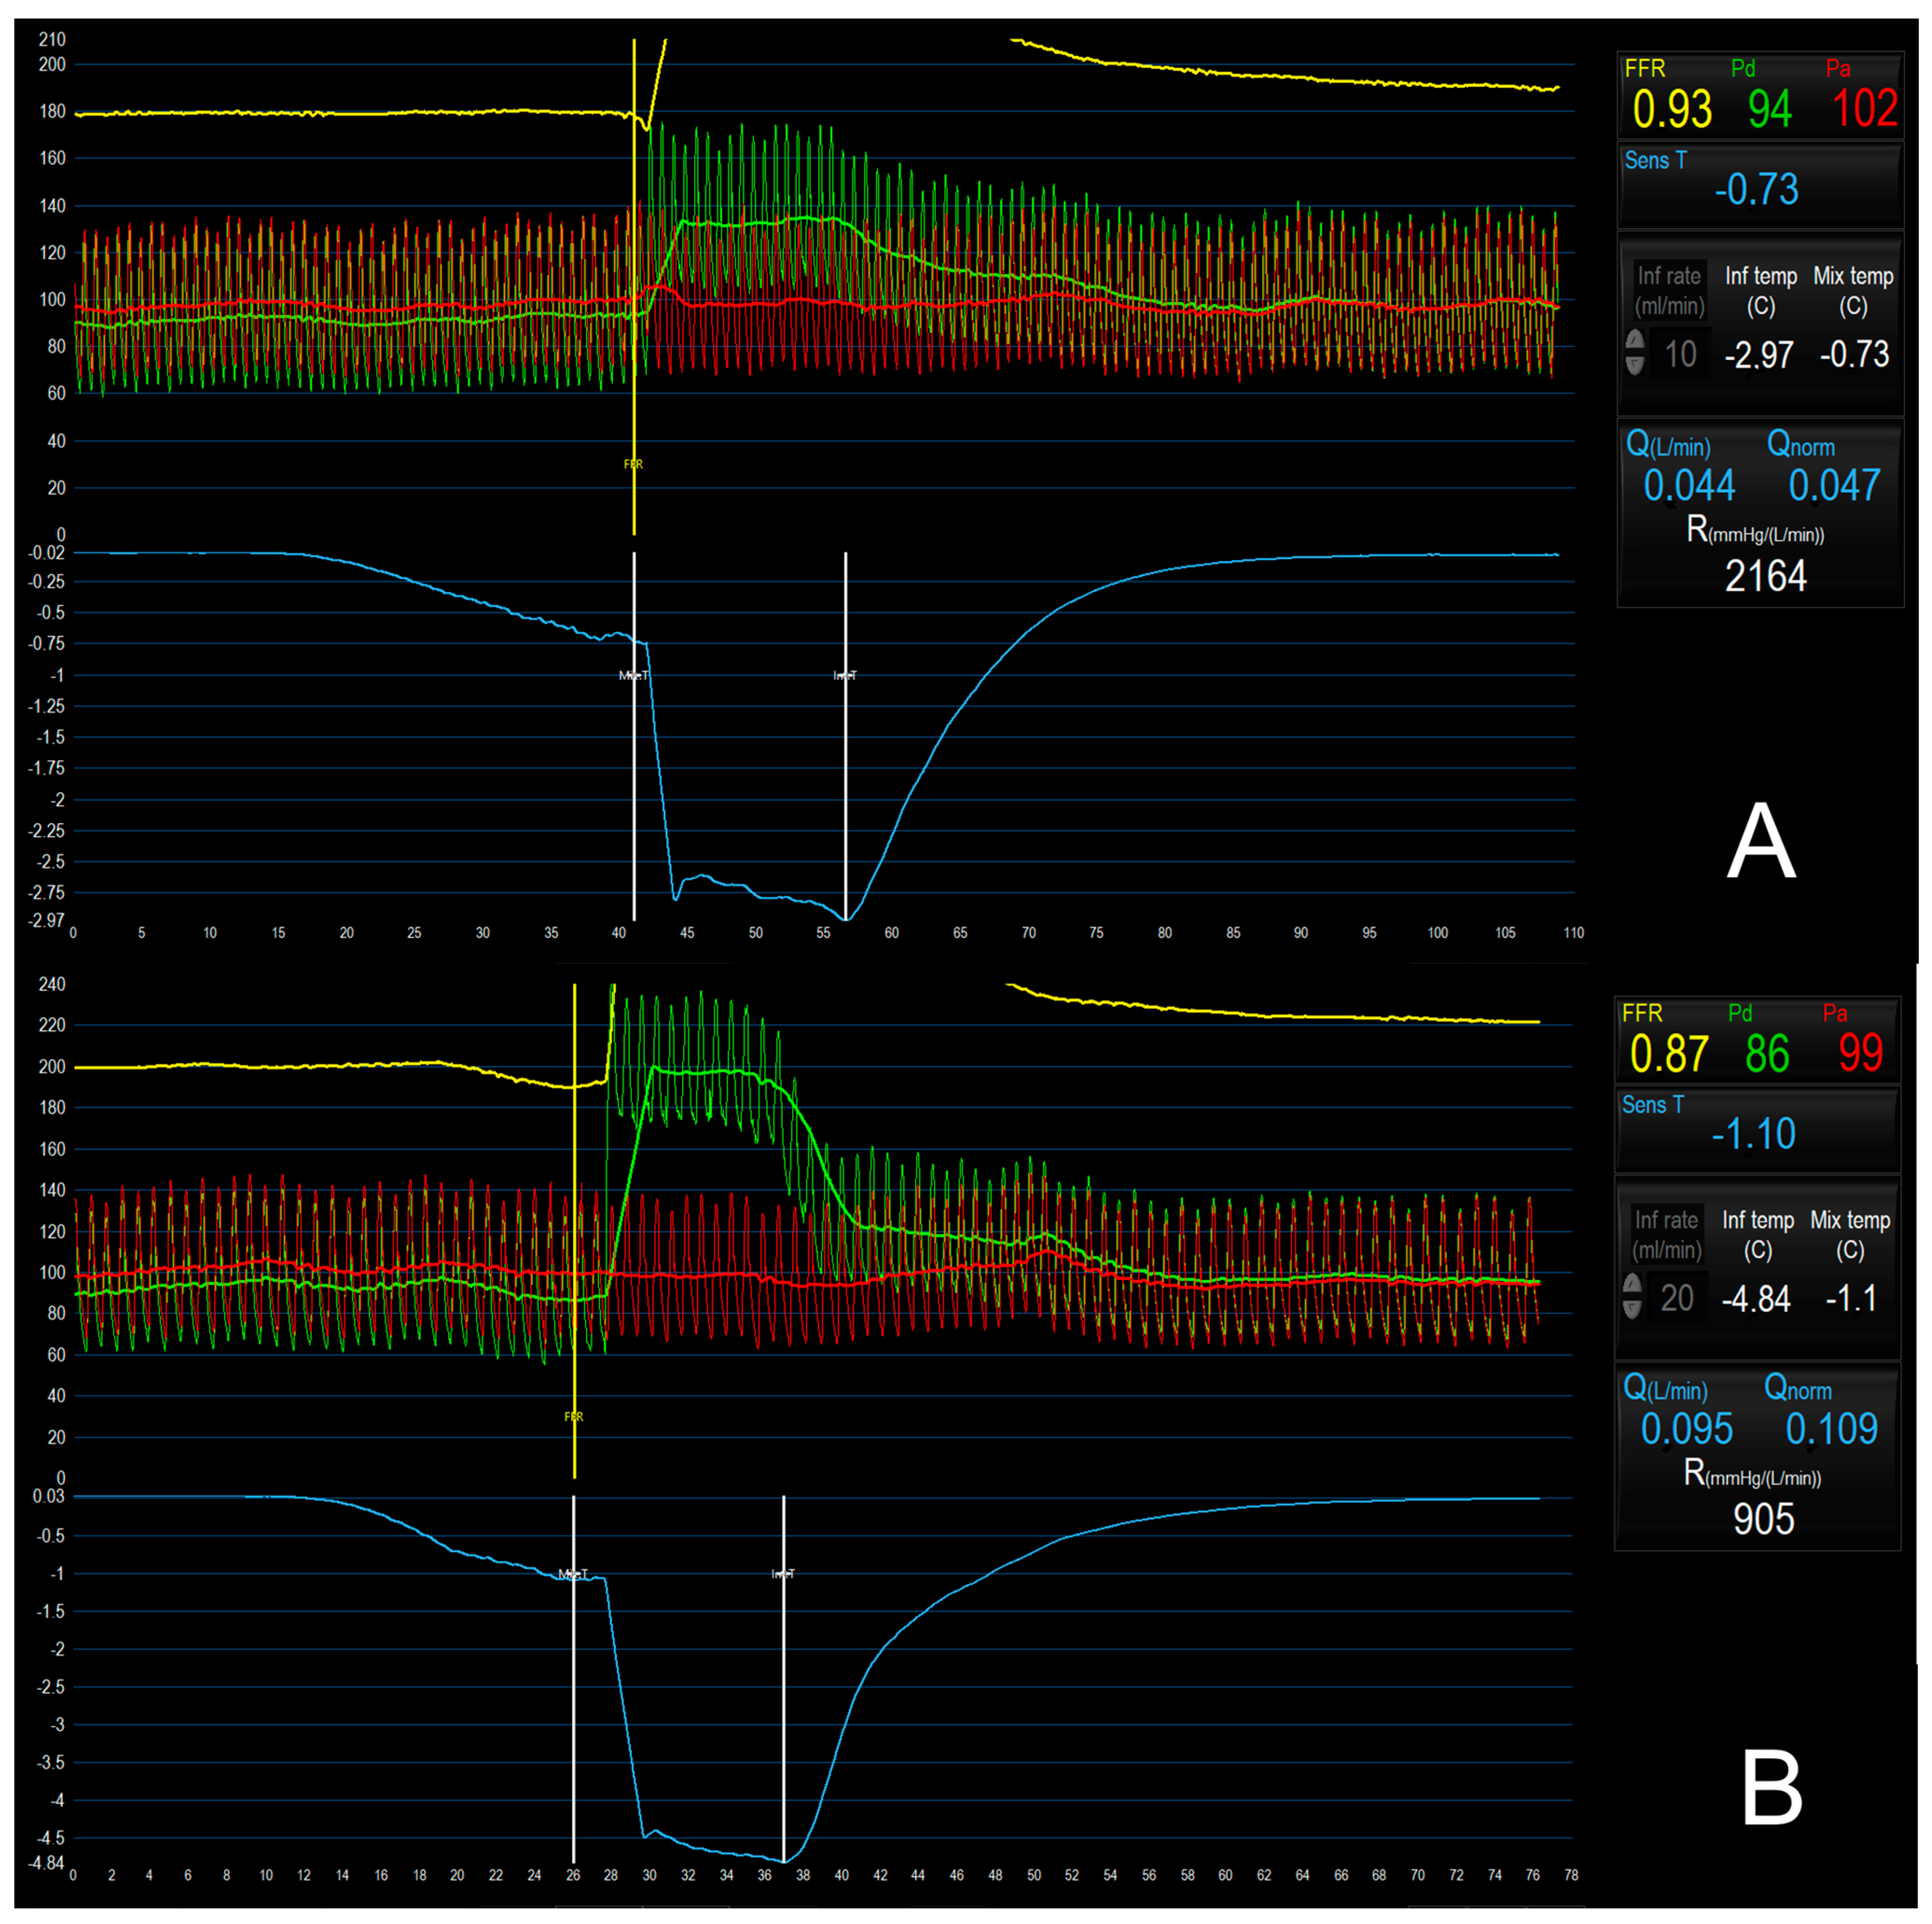

5.5. Bolus vs. Continuous Thermodilution Method to Assess CMD

- Gallinoro, E.; Bertolone, D.T.; Fernandez-Peregrina, E.; Paolisso, P.; Bermpeis, K.; Esposito, G.; Gomez-Lopez, A.; Candreva, A.; Mileva, N.; Belmonte, M.; et al. Reproducibility of bolus versus continuous thermodilution for assessment of coronary microvascular function in patients with ANOCA. Eurointervention 2023, 19, e155–e166. [Google Scholar] [CrossRef] [PubMed]

| Bolus thermodilution | Coronary flow reserve (CFRbolus) | CFRbolus | <2.0 (validated) | The capacity to increase CBF from resting to stress conditions (derived from transit time). |

| Index of microvascular resistance (IMR) | IMR = | ≥25 (validated) | Dimensionless index which represents MVR during stress conditions. | |

| Resistive reserve ratio (RRR) | RRR = | Unknown | The ability of microcirculation to reduce MVR during stress conditions (derived from transit time). | |

| Continuous thermodilution | Absolute coronary flow (Q) | Q = | <200 mL/min (under investigation) | Direct measurement of CBF. |

| Absolute microvascular resistance (R) | R = | >500 UW (under investigation) | True MVR derived from CBF. | |

| Coronary flow reserve (CFRcontinuous) | CFRcontinuous = | <2.0–2.5 (under investigation) | The capacity to increase CBF from resting to stress conditions (derived from CBF). | |

| Microvascular resistance reserve (MRR) | <2.1 (under investigation) | The ability of microcirculation to reduce MVR during stress conditions (derived from CBF). |